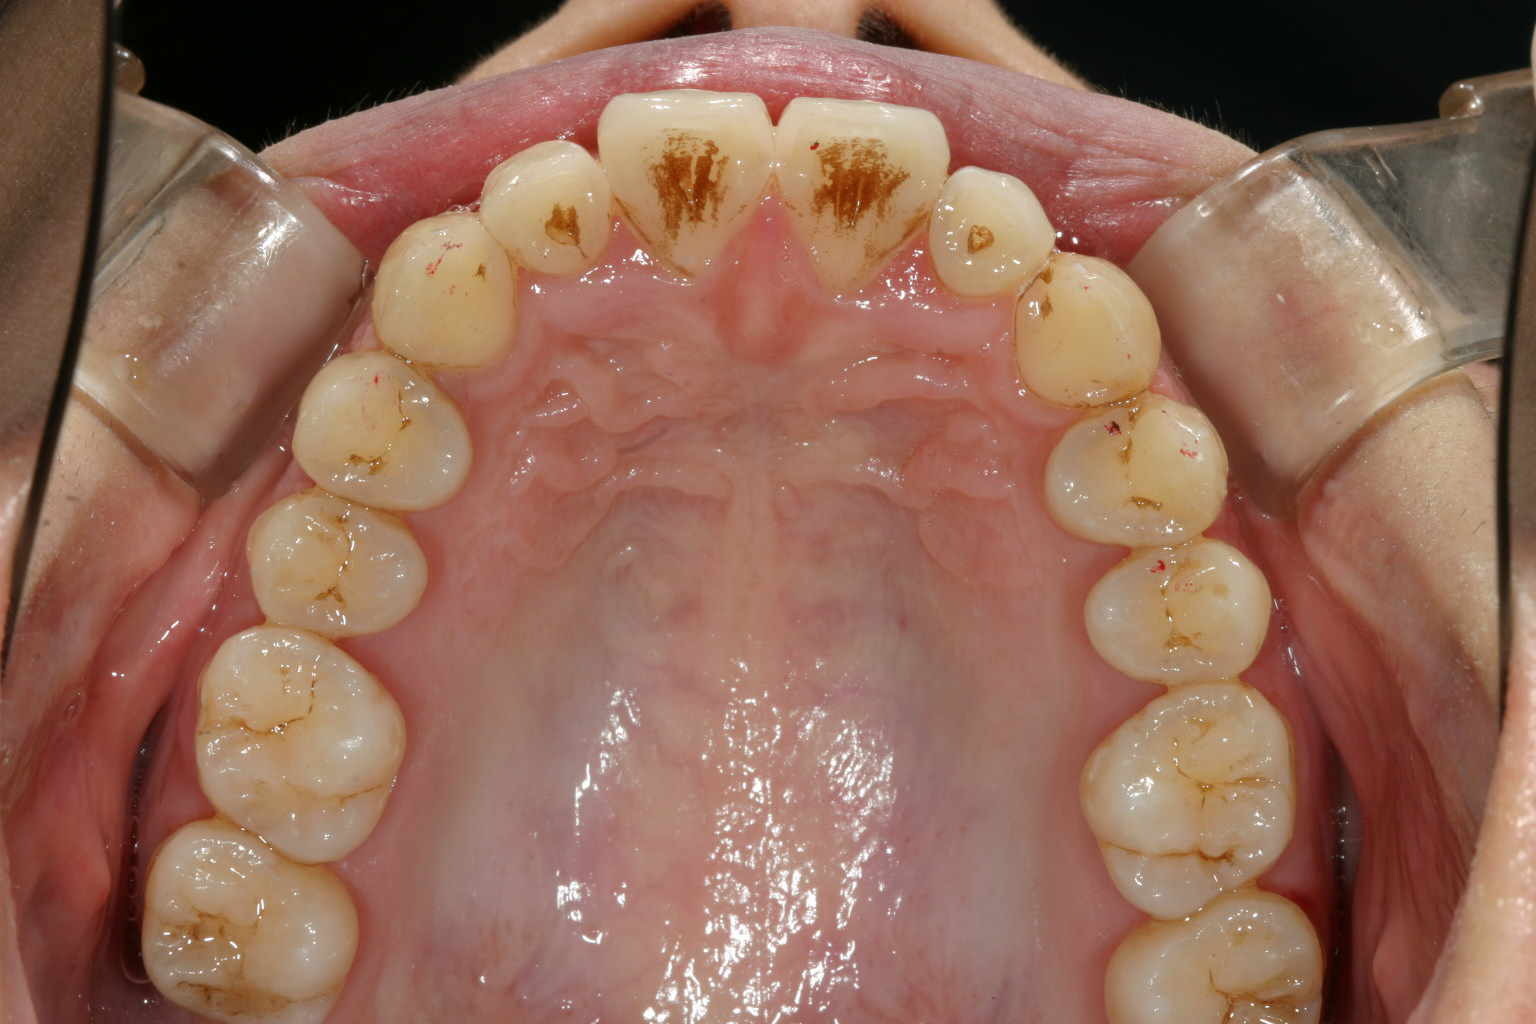

綺麗なアーチに改善いたしました。

かなりヘビーな翼状捻転です。

下顎前歯の叢生もかなりのもんです。 と言う事でワイヤー矯正を選択しました。